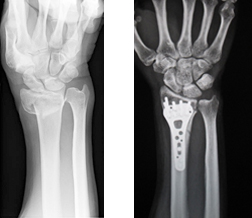

①橈骨遠位端骨折粉砕の強い場合、関節内に骨折が及ぶ場合は手術を行います。プレートを用いた整復固定を行いますが、粉砕の強い場合は創外固定や人工骨充填を併用します。

手術前 手術後

手指の小さい骨の骨折においては初期治療が極めて重要です。手術が必要かどうかの見極めが時に難しく、専門医のもとを受診され治療方針を決定することをおすすめします。当院では外傷の程度や患者の年齢、社会背景なども考慮し手術も含めた最善の方法を選択しています。手術時に用いる器械は手指に特化した特殊なものを用いて、より正確な整復を心がけています。